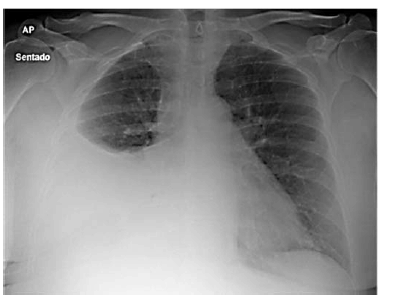

Paciente do sexo feminino, de 27 anos de idade, casada, técnica de enfermagem de uma unidade de pronto atendimento (UPA), comparece ao setor de emergência com queixa de dispneia havia 1 semana e indisposição, havia 1 mês. Era tabagista ativa e não fazia uso de medicações regularmente. Na história ginecológica da paciente, não havia particularidades, a anticoncepção era realizada com preservativo masculino. Ao exame físico, apresentou-se em bom estado geral, hidratada e com sinais vitais estáveis. ausculta pulmonar, o murmúrio estava abolido no terço inferior do hemitórax direito. Nos exames complementares, o hemograma estava normal, as sorologias negativas. A imagem a seguir mostra o Raio X de tórax da paciente.